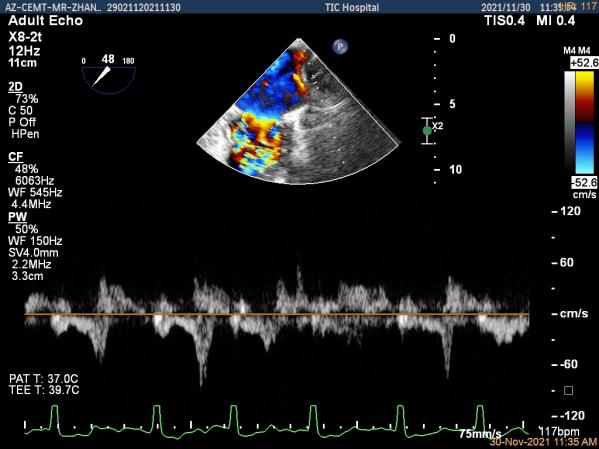

第一个夹子放置侯二尖瓣口平均跨瓣压差:4mmHg

肺静脉血流频谱恢复正向